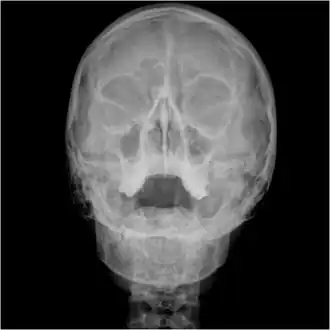

![]() Waters view showing diffuse prominent mucosal thickening in the right maxillary sinus and mild nmucosal thickening in the left maxillary sinus. | |

Orbital x-ray or orbital radiography is an x-ray of both left and right eye sockets, to include the Frontal Sinuses and Maxillary Sinuses.

An orbital x-ray usually requires only one view unless the requester is looking for evidence of metallic fragments, in which case two projections can be made. One with the eyes looking up, one with the eyes looking down. These views will show any movement of fragments and helps rule out false positives / artefacts which may be present on the image receiver. Two other important views are the Water's view which helps visualise the anterior orbital floor and maxillary sinuses; and the Caldwell view which helps to visualise the frontal and ethmoid sinuses and posterior orbital floor.[3]